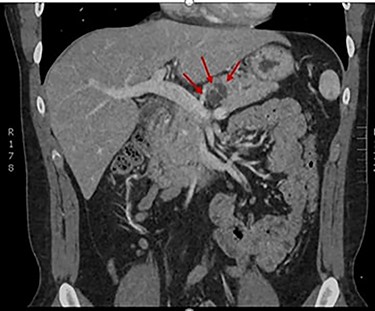

The patient is a 21-year-old male who presented for surgical consultation after his second hospitalization for acute pancreatitis over a 6 month period. During his most recent admission, magnetic resonant imaging (MRI) demonstrated a 2.2 cm cyst in the pancreatic body with dilatation of the main pancreatic duct to 5 mm suggestive of a mixed duct IPMN (Fig. 1). Presence of two ‘worrisome’ features, which included lesion size >2 cm and main duct dilation >5 mm according to the Fukuoka 2017 management guidelines, prompted a referral for endoscopic ultrasound (EUS) and cyst aspiration with pathologic fluid analysis [7]. A laboratory workup was performed, to include carbohydrate antigen 19-9, carcinoembryonic antigen and pancreatic islet antibody.

The patient received vaccinations preoperatively against encapsulated organisms to include Streptococcus pneumoniae, haemophilus influenzae type b and meningococcus. A dedicated pancreas protocol computed tomography scan was performed for operative planning, which demonstrated interval increase in the size of the cyst to 2.4 cm (Fig. 2). On the day of surgery a robotic-assisted laparoscopic distal pancreatectomy was performed. We elected to perform a splenectomy because the splenic vasculature was found to be densely adhered to the posterior aspect of the pancreas secondary to repeated bouts of pancreatitis. The distal pancreas and spleen specimen, along with 21 lymph nodes, were removed en bloc. Final pathology demonstrated a 1.4 cm IPMN with low-grade dysplasia involving the branch ducts and focal high-grade dysplasia involving the main duct. No invasive malignant component was identified in the specimen and all examined lymph nodes were benign. The patient had an uncomplicated recovery and was discharged on postoperative Day 5 following drain removal. Completion of his post-splenectomy vaccinations were confirmed at his initial follow-up clinic visit. The patient will report for an additional follow-up with active surveillance imaging in 6 months.

CT demonstrating resolution of pancreatitis and interval growth of IPMN to 2.4 cm.